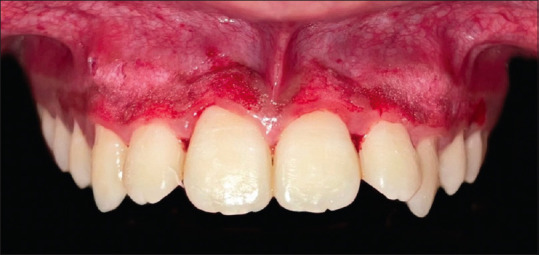

Abstract Image